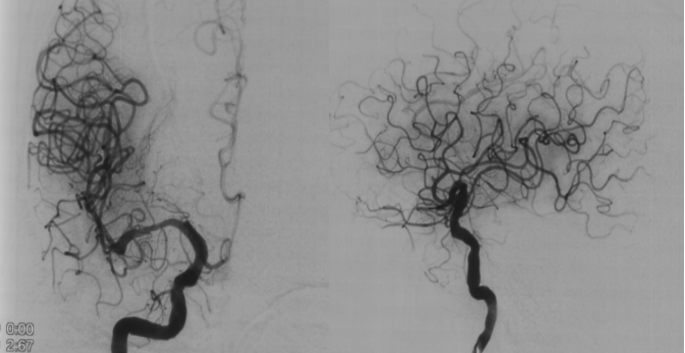

Gateway 2.5/15球囊预扩 6atm;Sequent please 2.5/15 5 atm药物球囊扩张成形

球囊扩张后造影,术后患者症状明显改善